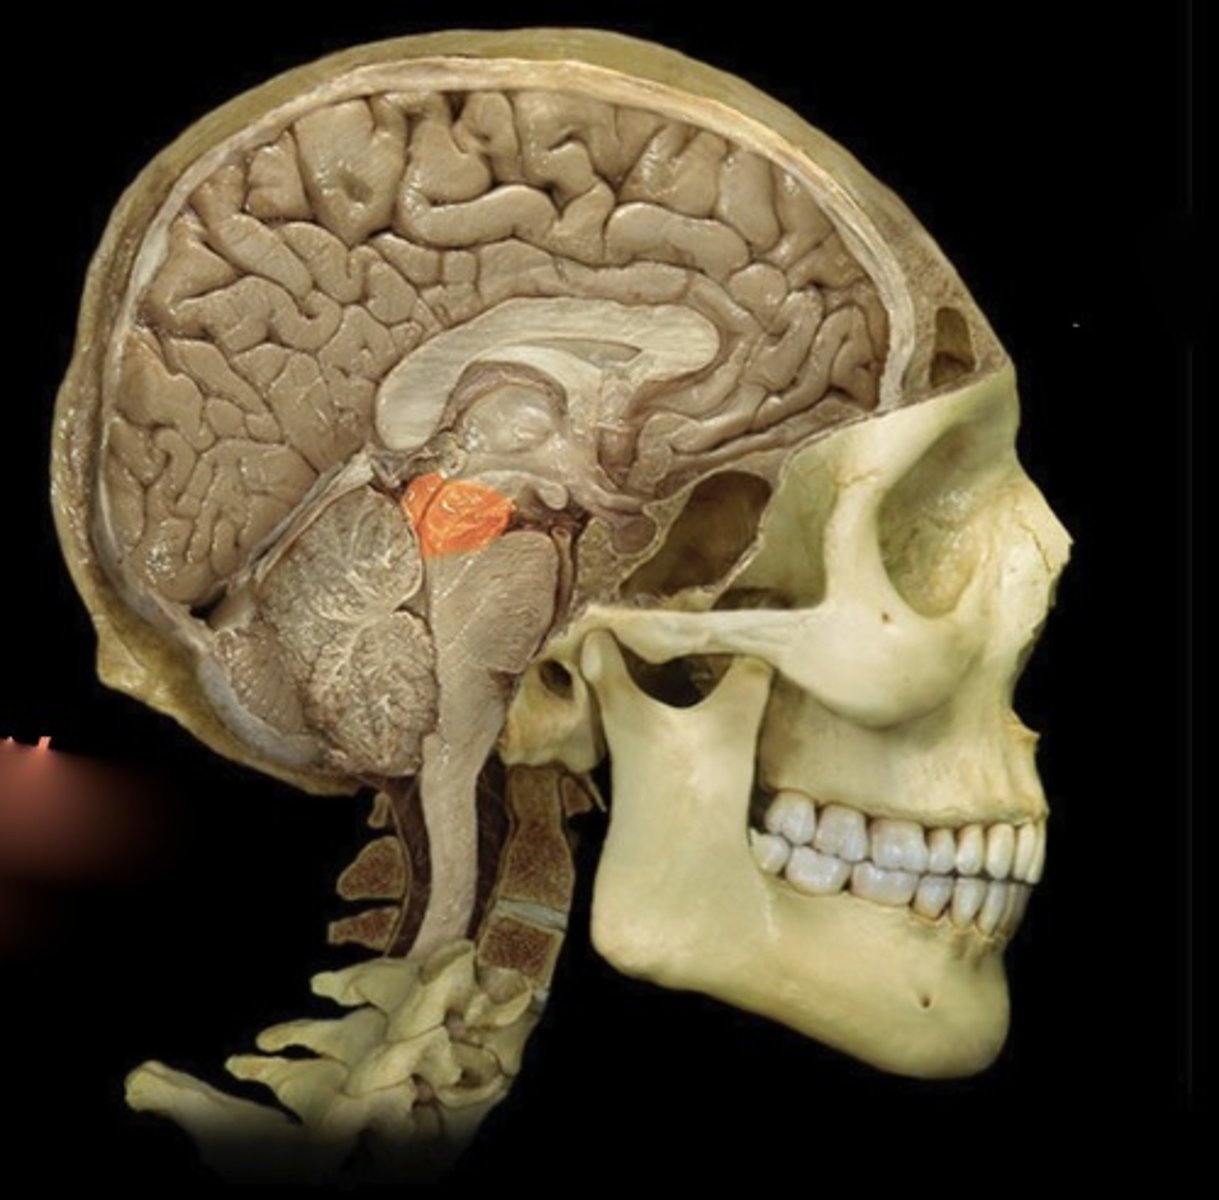

Diencephalon (of an isolated brain)

Name this structure

Thalamus

Name this structure

Hypothalamus

Name this structure

Pineal gland

Name this structure

Mamillary Body

Name this structure

Pituitary gland

Name this structure

Midbrain

Name this structure